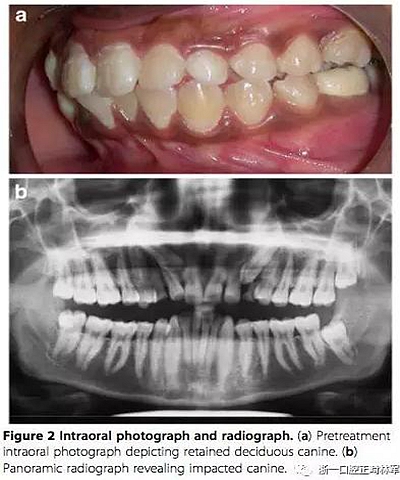

患者女,16歲,主訴:下牙列擁擠。

左上乳尖牙未脫落,全景片示左上尖牙頰側(cè)阻生。